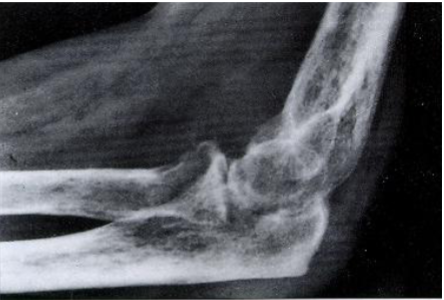

Rheumatoid Arthritis

Juxta-articular erosions (lysis of bone/osteopenia)

Joint ankylosis

Juxta-articular bone erosions